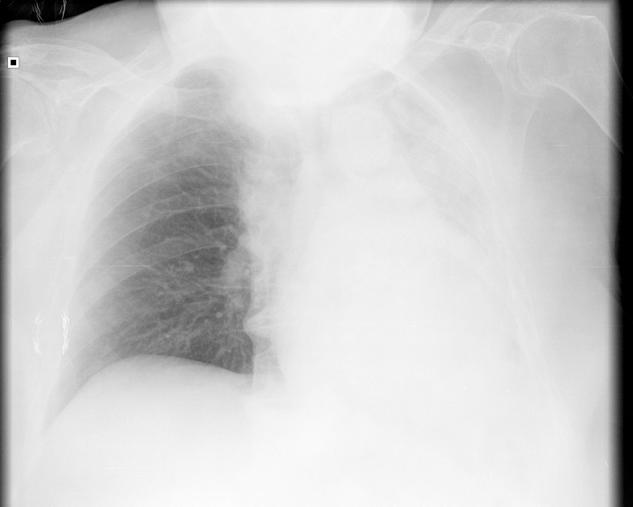

[Atelectasis due to a mucus plug resolved conservatively].

[Atelectasis due to a mucus plug resolved conservatively].因黏液栓导致的肺不张经保守治疗后缓解